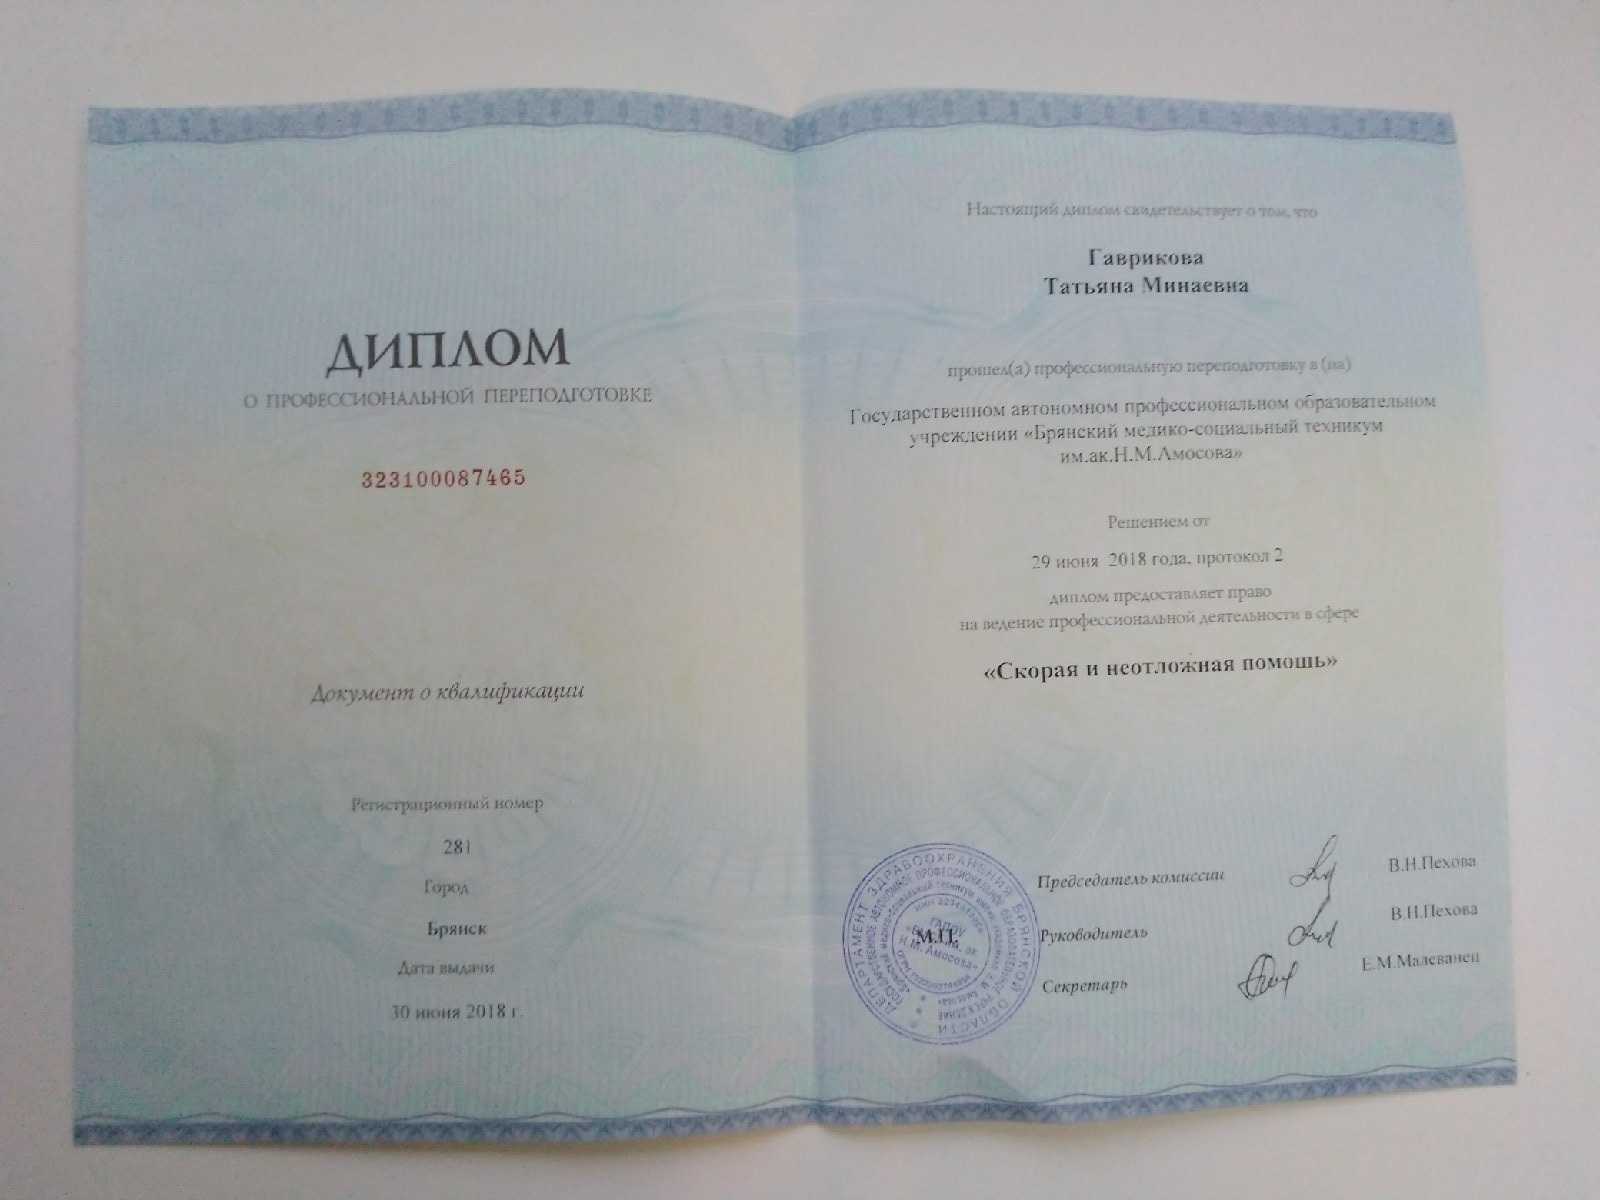

Автор материала Татьяна Гаврикова

Фельдшер

Училась в ГАПОУ Брянский медико-социальный техникум им. академика Н. М Амосова